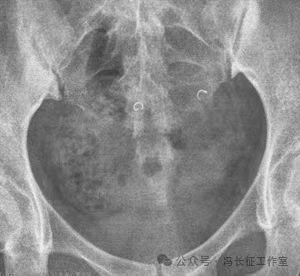

平片显示盆腔内2个C形高密度影为弹簧圈

微信图片_20240223171417(6).jpg